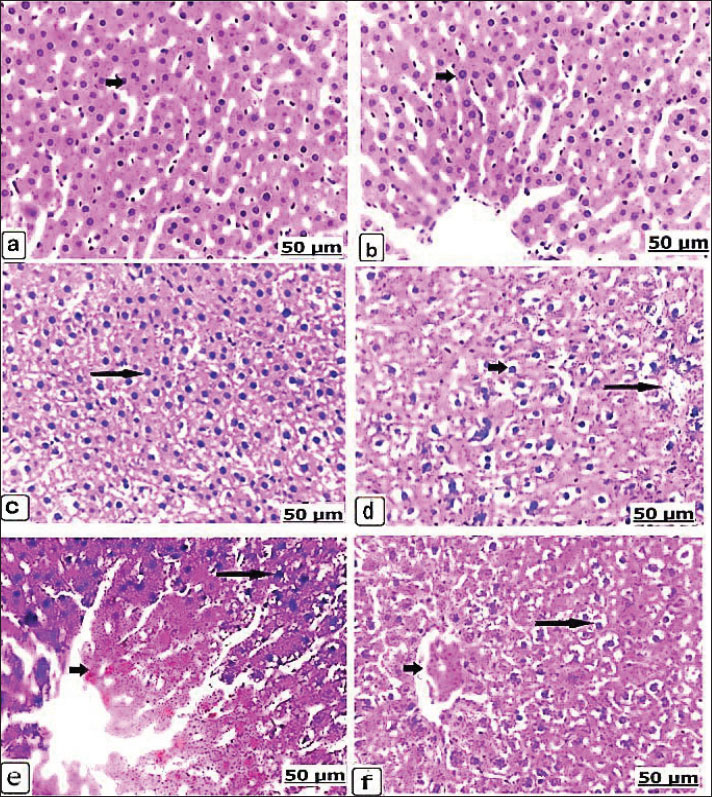

Fig. 5. (a–d). Light photomicrographs of the brains of the control and experimental groups for 21 days, stained with hematoxylin and eosin. Control non-pregnant C2(21) and control pregnant A2(21) showing normal neuron architecture (a and b). Group D1(21) received 625 μg of dexamethasone for 21 days, showing neuronal necrosis with perineuronal vacuolation (long arrow) and edema and dilatation in the Virchow robin space (short arrow) (c). Group B1(21) received 625 μg of dexamethasone for 21 days, showing perineuronal vacuolation (long arrow) and thrombotic vasculitis (short arrow) (d). Microscopic kidneyAfter 14 days, H&E staining of the kidneys of the control groups showed intact kidney tubules with normal organization (Fig. 6a,b). While there was edema and congestion of the blood vessels of the kidneys of the non-pregnant rats who received 625 µg dexamethasone (Fig. 6c), this congestion became extensive with thickening of blood vessels when the pregnant rats were administered a similar dose. In addition, necrosis of renal tissues with edema and congestion of the interstitial blood vessels, as well as hypercellularity of the glomeruli, was found (Fig. 6d). When the non-pregnant group was exposed to 125 × 10 µg of dexamethasone, severe renal tubule necrosis and interstitial fibrosis expressed (Fig. 6e), and sharp renal tissue necrosis occurred in the pregnant group (Fig. 6f). After 21 days, Kidney histology revealed the kidney structures of the normal renal tubules of the control non-pregnant (Fig. 7a); in parallel, the control pregnancy showed an ideal arrangement of the kidney tubules and collecting duct (Fig. 7b). Kidney lesions after receiving 625 µg dexamethasone showed interstitial fibrosis of the renal tubules with marked deposition of the fibrous tissues, besides renal necrosis beside edema, and congestion of the interstitial blood vessels, in non-pregnant and pregnant females (Fig. 7c,d).

Fig. 7. (a–d). Light photomicrograph of the kidneys of the control and experimental groups stained with H&E for 21 days. Control non-pregnant C2(21) showed normal renal tubules (arrow) (a); likewise control pregnant A2(21) showed an ideal arrangement of collecting duct and tubules (arrow) (b). Group D1 (21) received 625 μg of dexamethasone for 21 days, showing interstitial renal tubule fibrosis (arrow) (c). Group B1(21) received 625 μg of dexamethasone for 21 days, showing edema and congestion of the interstitial blood vessels (short arrow) (d). Microscopic spleenAfter 14 days, the control spleen of the non-pregnant groups showed the normal structure of white and red pulps (Fig. 8a), and the splenic tissues of the pregnant control group showed the ideal organization of the white and red pulps (Fig. 8b). Conversely, the non-pregnant rats received 625 µg of dexamethasone, showing gradual depletion and reduction of lymphoid follicles (Fig. 8c), whereas the pregnant groups showed intensive red blood cell infiltration with remarkable splenic trabeculae protrusion correlated with intense hemosiderosis and white pulp lymphocyte depletion (Fig. 8d). Additionally, the non-pregnant spleen received 125 × 10 µg of dexamethasone and exhibited observable hemorrhage and hemosiderosis in the red pulp characterized by mixed infiltration of red blood cells and hemosiderin, as well as lymphocytic depletion of the lymphoid pulps (Fig. 8e). These lesions were observed in pregnant rats that received 125 × 10 µg dexamethasone; moreover, vasculitis with thickening and inflammation of the blood vessel wall was observed (Fig. 8f). After 21 days, non-pregnant animals in the control group had normally arranged splenic pulps (Fig. 9a), similar to the control spleen of pregnant animals (Fig. 9b). Non-pregnant spleen, when administerted 625 µg dexamethasone, displayed a remarkable degree of hemorrhage characterized by erythrocyte infiltration of the red pulp, as well as a scattered form of hemosiderosis (Fig. 9c), and brown particles of hemosiderin also appeared in the pregnant rat’s spleen of the same category dose (Fig. 9d).